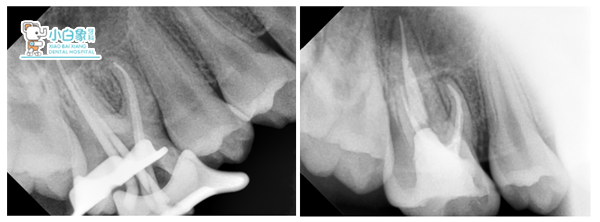

治疗过程:16必兰麻下去腐质揭髓顶大量渗出,丁香油棉捻安抚后封慢失一周。复诊16叩(土),去暂封,拔髓,腭侧及远中颊侧根长19mm,近中颊侧及MB2长18mm,M3预备,常规冲洗,隔湿干燥,热牙胶充填,Z350充填。

各根管口的形态是:近颊根管口较扁,若其再分为颊、舌两根管口,两根管口较圆小,近颊根管的舌侧根管口位于远颊根管口的舌侧,距舌根内的舌侧根管口最近,远颊根管口略圆,舌侧根管口较宽大。近颊根管为双管型或单双管型者共占63%,远颊侧根管分为两管者占9%,舌侧根管较宽大。